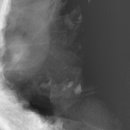

• 뿌리동물병원 치과센터 | 고양이 치주염, 송곳니 골염으로 인한 수원 뿌리동물병원 고양이 치과 예진 후기 + 신부전 초기 발견?!

🐈 ​ 더이상은 미룰 수 없었던 춘장이의 발치수술..🦷 괜찮다는 동물치과전문병원 찾고 찾아 드디어 방문하게 된 수원의 뿌리동물병원 예진 후기! ​ ​ ✔️춘장이의 이빨 상태와 발치 수술을 결정하게 된 계기 ​ 23년도쯤부터 춘장이 왼쪽 윗 송곳니의 잇몸이 점점 부풀어오르더니 색도 점점 빨개졌다.. ​ 양치를 매일같이 해줘도...

ᕷ ᴘɪᴋᴏᴘɪᴋᴏ | ʙᴀʙʏ&ᴅᴀɪʟʏ ᕷ(2025-10-11 10:50:00)